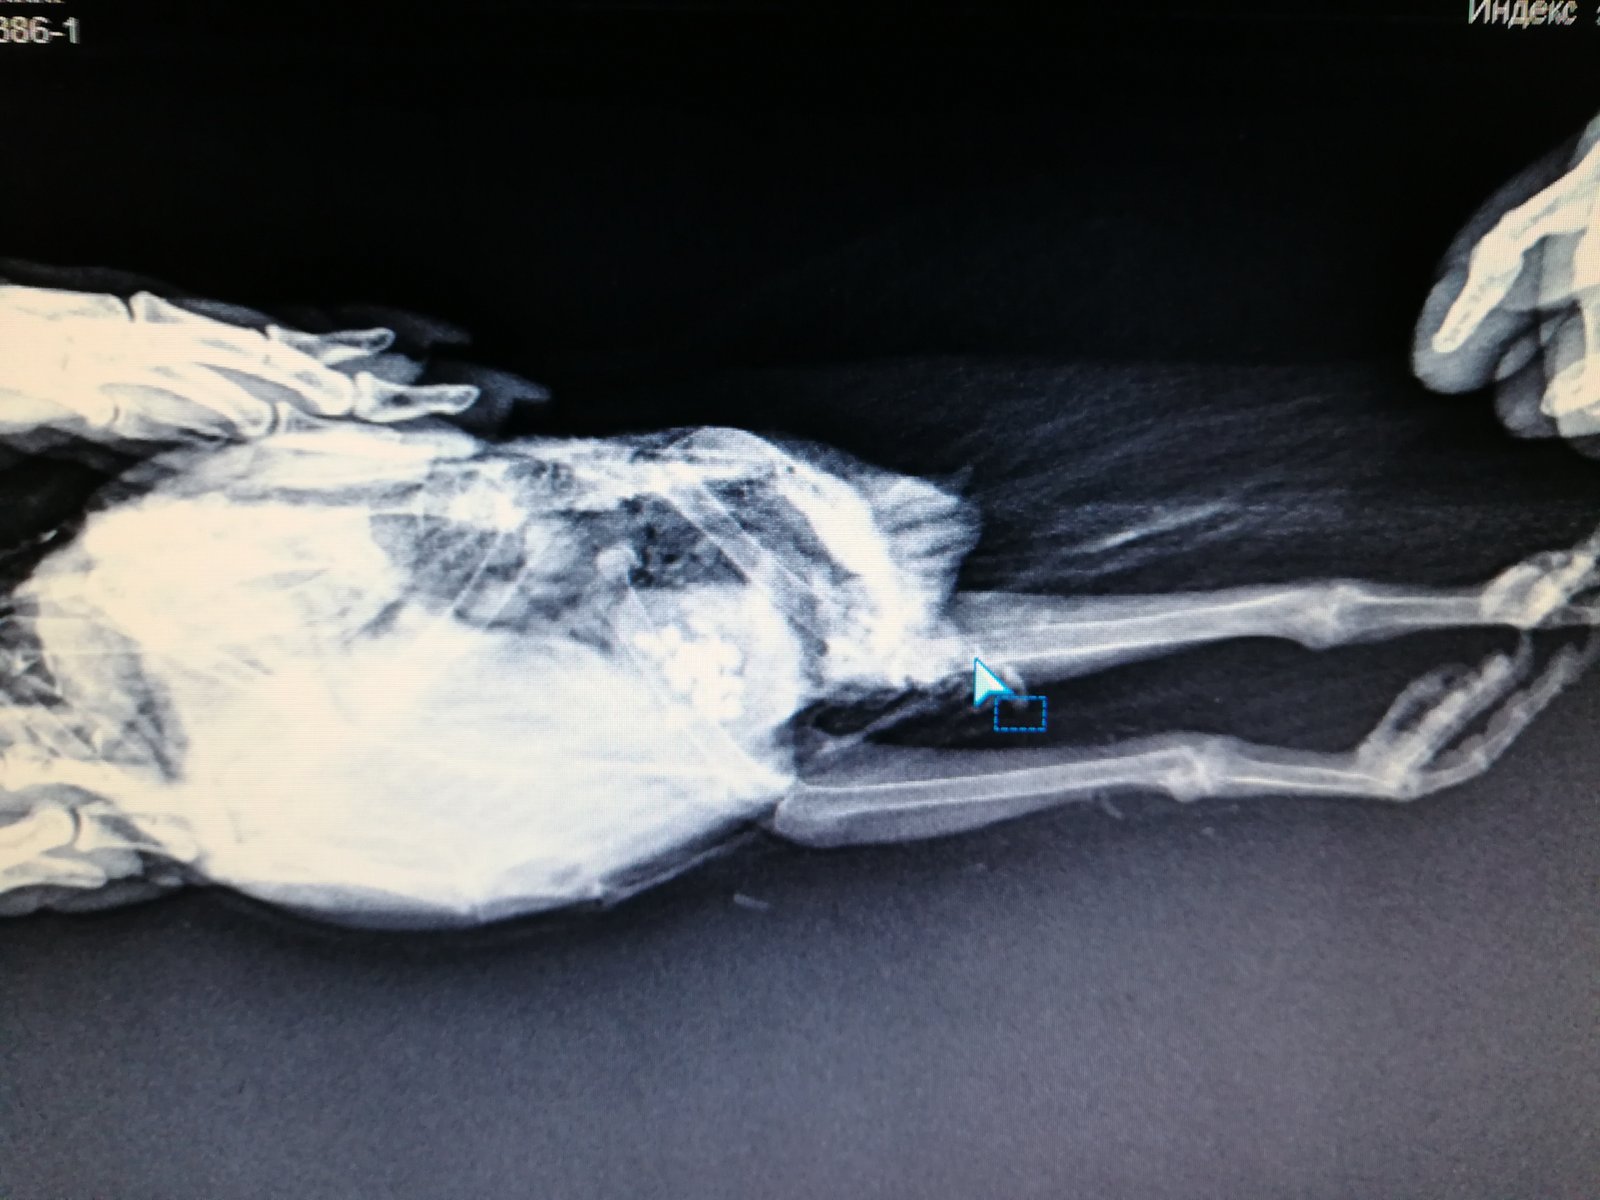

Elena1811 Опубликовано 7 марта, 2020 Автор #113 Опубликовано 7 марта, 2020 Мы старались как могли. Не получается его развернуть полностью из-за левого крыла. Не разворачивается доконца. Боялись сломать

Elena1811 Опубликовано 7 марта, 2020 Автор #115 Опубликовано 7 марта, 2020 5 минут назад, маленький принц сказал: позвал в тему Зосю Спасибо. Будем ждать. И надеюсь снимки читабельны

Elena1811 Опубликовано 7 марта, 2020 Автор #116 Опубликовано 7 марта, 2020 Нам их дополнительно скинули на флэшку

Zosia Опубликовано 7 марта, 2020 #124 Опубликовано 7 марта, 2020 Если есть файлы на флешке- то мне на почту киньте. Т.к. в переснятом виде снимки нечитабельны. zofia68@mail.ru

Elena1811 Опубликовано 11 марта, 2020 Автор #130 Опубликовано 11 марта, 2020 Получила ответ от Зофии. Нужны разъяснения. И некоторые препараты я не могу купить Вот что пишет Зофия: Ну, отличить голубя от голубки я по фото не смогу. Хотя ИМЪО мне видится голубка. И те новообразования в брюшной полости (которые могцт передавливать нервные окончания, идущие к лапкам)- характерны именно для голубок, у меня даже фото есть гранулем, которые у них «рождаются» вместо яиц. Так что ИМХО- итраконазол в дозе 15 мг/кг каждые 12 чсов, нисиатин в дозе 75 000 ед в сутки на 100 гр веса, преднизолон из арсчета 3 мг/кг в сутки. Первый курс- 21 день. Для прикрытия преднизолона- Деринат капли назальные, принимать орально 4 капли в сутки весь курс. Обязательно гепатовте- 0,2-0,3 мл в сутки. По крылу- ваш снимок не дает возможности оценить фатальность нарушений. Но скорее всего- там уже вряд ли что можно сделать (и по-любому это вопрос-не вопрос жизни). ......... У нас беда с преобретением лекарств, рецепты только лишь на аналгин не нужны..